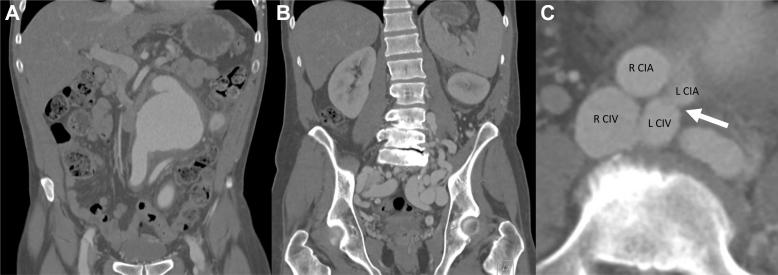

Staged endovascular repair of an abdominal aortic aneurysm adjacent to a chronic high-flow iliocaval traumatic arteriovenous fistula.

Large-vessel chronic traumatic arteriovenous fistulas are a rare complication after trauma. Delayed presentation can consist of one or more features of high-output cardiac failure, pulsatile abdominal mass, bruit, limb ischemia, and venous congestion. We describe a patient with a complex iliocaval fistula secondary to a remote gunshot wound associated with a large 8.5-cm aortic aneurysm. Informed consent of the patient was obtained for publication of the case.